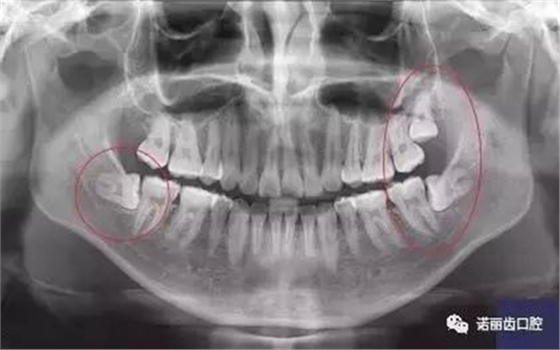

那么,如何判斷自己的智齒生長情況呢?除了有明顯的疼痛感你需要做相應的處理,同時通過X線可以觀察智齒的數(shù)量和位置以及具體情況。

經(jīng)過拍片探查,確定了以下情況的,那么,果斷的,禍患不可留?。?/p>